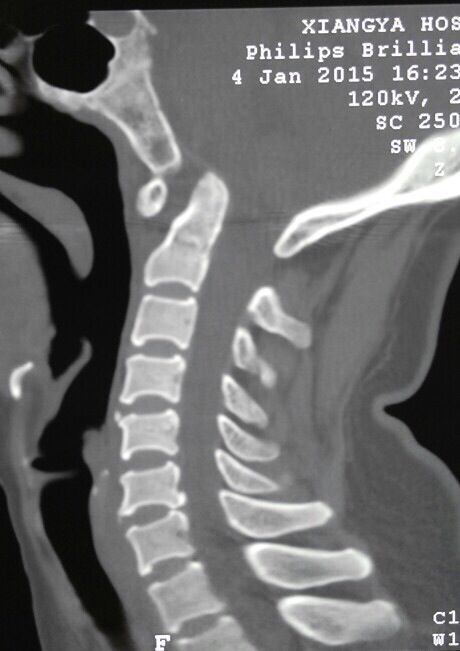

颈椎MRI,CT显示寰枢椎脱位,小脑扁桃体下疝,脊髓空洞